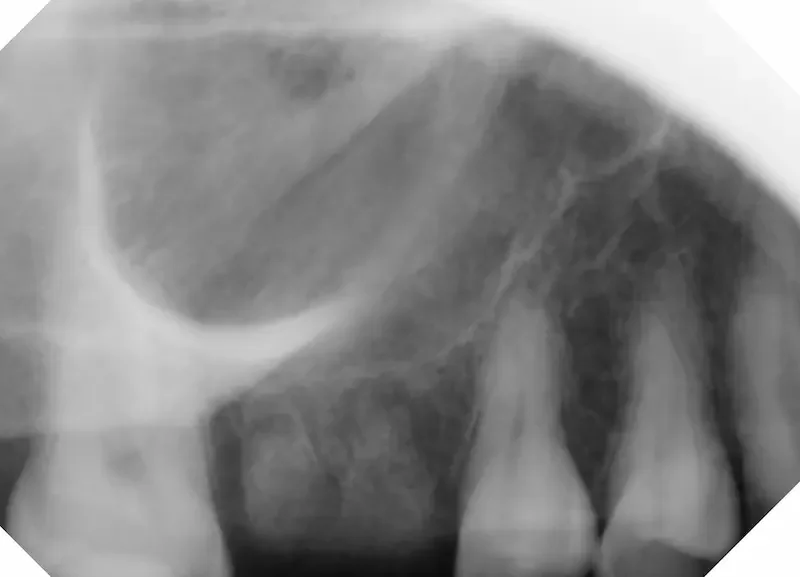

This case involved tooth #3, an upper molar that had an abscess caused by a large cavity. The tooth was broken at the gumline. The tooth had an old root canal as well.

Before the tooth was removed, there was an abscess visible in the X Ray. This tooth was broken at the gumline for some time, but not bothering the patient (it was not causing pain, and she could chew comfortably with her remaining teeth). But she was aware of the risks with an abscess like this, and wanted to get it taken care of.

The risks in not treating a tooth abscess:

While this tooth wasn’t causing pain at the time, the X-Ray shows a periapical abscess (infection around the roots). This is a bacterial infection that will not resolve on its own and, if left untreated, can continue to spread beyond the tooth and surrounding bone. In some cases odontogenic infections extend into adjacent tissues and fascial spaces, potentially leading to complications such as facial swelling, airway compromise, systemic spread (including sepsis), sinus involvement, osteomyelitis of the jaw, and other serious outcomes documented in the dental literature when abscesses are not definitively treated. In other words, there’s risk an infection like this “blows up” and causes significant damage.¹ ² ³

X Ray before Extraction. Notice the darker area around the roots of the root canal treated tooth- that’s where the infection is.